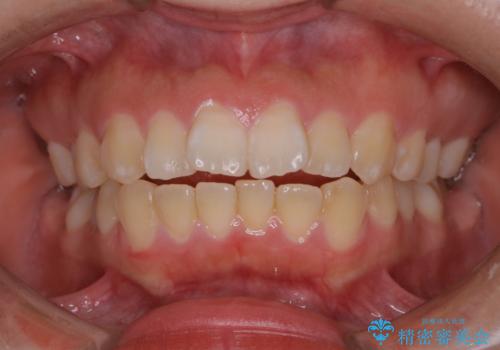

前歯の乱れをスッキリ解消!抜歯矯正で整えた美しい歯並び

担当医 河口智英